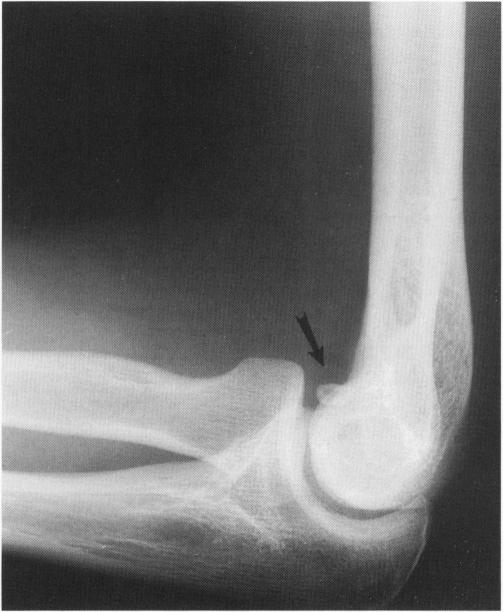

Bilateral osteochondritis dissecans in a female pitcher. A case report and review of the literature.